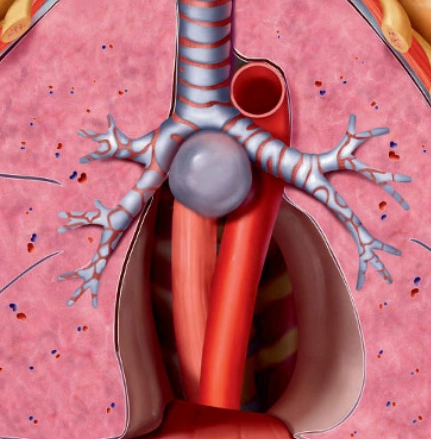

Phình động mạch chủ ngực (Thoracic aortic aneurysm)